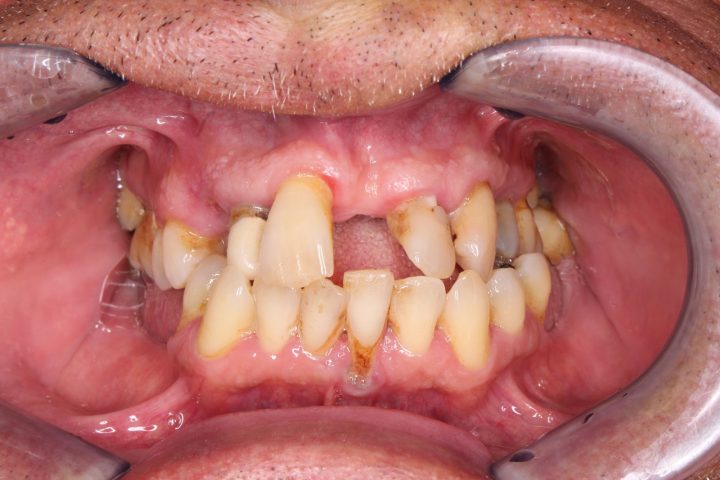

Daniel

Daniel ist ein 54-jähriger Lastwagenfahrer. Seit seiner Kindheit hatte er schlechte Zähne, bis er in die Klinik kam, alle fallen raus.

Aufgrund von der CT- Aufnahme haben wir mit dem Patienten zusammen entschieden, dass wir 4-4 Alpha Bio Implantate in Ober- und Unterkiefer einsetzen.

Die Operation dauert zweimal 1,5 Stunden lang, und wurde der provisorische Zahnersatz im Ablauf den 5 Tagen fertig. Nach der 3 Monate langen Heilungszeit wurden zwei Stegprothesen auf 4-4 Implantate befestigt.

Die Implantatprothese sichert die Stabilität für den Patienten, so konnte Daniel am Ende der Behandlung wieder Steak essen, was sein Traum war.